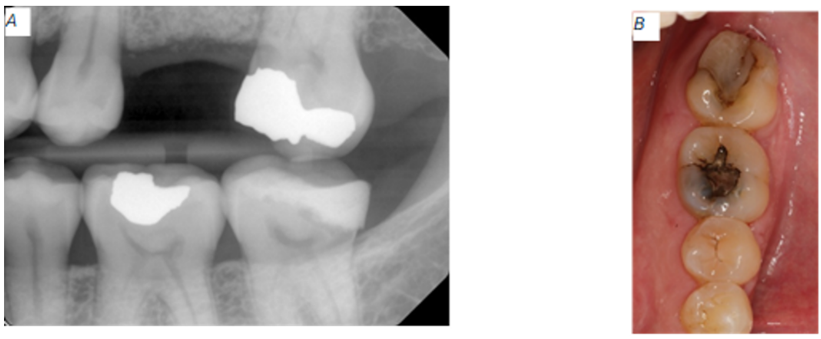

On June 3, 2024, a 50-year-old female patient presents to the Keller Army Community Hospital Dental Clinic Periodontics Department at West Point New York with a chief concern (CC): “the prosthodontist told me that I needed surgery to receive a crown on my lower left tooth. I am also missing a tooth on the upper left and I would like an implant for that gap.” Her medical history is significant for gastroesophageal reflux disease (GERD), exercise-induced asthma (EIA), and perennial allergic rhinitis (PAR). She takes cetirizine, pantoprazole, and montelukast every day, but levalbuterol as needed. Review of her medical chart confirms allergies to nickel, lanolin, and sulfa drugs. Nickel and lanolin allergies were diagnosed using a skin patch test. During her initial evaluation, she made it clear that she has irrational dental anxiety and worse yet, surgical phobia. She has a Mallampati class 4 airway. She has been diagnosed with nocturnal bruxism and wears a maxillary hard night guard to mitigate occlusal wear. The tooth on the maxillary left side is missing because it fractured below the alveolar crest and the oral surgeon had to take the patient to the OR to extract tooth #14 and performed an alveolar ridge preservation (ARP). In addition to the ARP, the oral surgeon performed a left lateral window maxillary sinus floor augmentation (LWSA) due to sinus pneumatization (Fig 1).

Figure 1: Baseline radiographic clinical appearance for site #14. (A) Catastrophic tooth fracture. (B) Four months after extraction of tooth #14. (C) Remaining allograft present at the extraction site.

Concerning the mandibular left side, tooth #18 presented with recurrent caries around a composite restoration that replaced the distolingual cusp. The distal margin of this composite projects apically beyond the cavity preparation and appeared to approach the crestal bone (Fig 2).